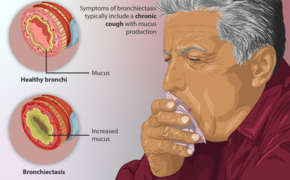

Read moreডা. মো: হোসনে সাদাত পাটোয়ারী, এমবিবিএস, এমডি (চেস্ট ডিজিজেস) শ্বাসতন্ত্র ও বক্ষব্যাধি বিশেষজ্ঞ, সহকারী অধ্যাপক, চমেক হাসপাতাল এটি একটি শ্বাসনালীর...